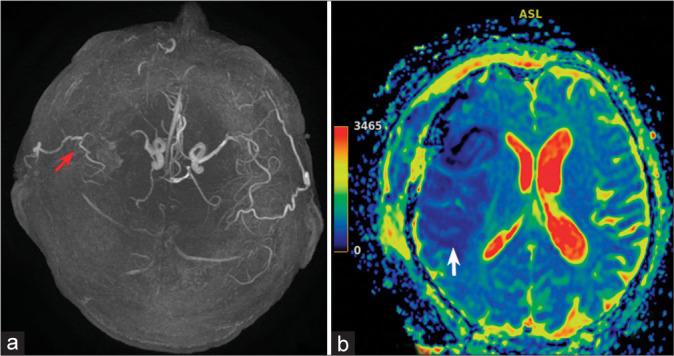

CASE DESCRIPTION

Clinical case of a 58-year-old man who developed an abscess in the chiasmosellar region and an associated mycotic aneurysm of the right middle cerebral artery (MCA) and intracerebral hemorrhage. Microsurgical clipping of the fusiform-ectatic aneurysm of the right MCA in the conditions of rupture was performed. An extra-intracranial micro anastomosis was formed on the right. An open biopsy of the neoplasm in the chiasmosellar region was made. The neoplasm was yellow and destroyed the bone plate of the skull base. Biopsy results: Mycotic lesion (aspergillosis). The analysis of surgical treatment for mycotic aneurysms in the acute period of hemorrhage in patients with aspergillosis revealed a high rate of lethality. The issue of the feasibility and effectiveness of complicated revascularization interventions in the patients with hemorrhage and aspergillosis remains unsolved.

一名58岁男性的临床病例,其在视交叉区域出现脓肿,并伴有右侧大脑中动脉(MCA)霉菌性动脉瘤和脑出血。在动脉瘤破裂的情况下,对右侧MCA的梭形扩张性动脉瘤进行了显微手术夹闭。在右侧进行了颅外-颅内微血管吻合。对视交叉区域的肿瘤进行了开放性活检。肿瘤呈黄色,破坏了颅底骨板。活检结果:霉菌性病变(曲霉病)。对曲霉病患者出血急性期霉菌性动脉瘤的手术治疗分析显示死亡率很高。出血合并曲霉病患者复杂血管重建干预措施的可行性和有效性问题仍未解决。